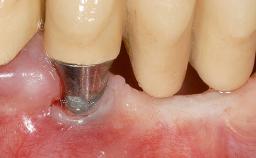

GBR and Soft-Tissue Augmentation Following Explantation to Rehabilitate a Soft- and Hard-Tissue Defect

It is sometimes necessary to remove and replace compromised implants. This case is a clear example of the need for multiple steps to achieve an optimal therapeutic result for patients with non-salvageable implants. It illustrates how the lost soft and hard tissues were rebuilt in a sequence that improved the healing of the hard tissues and assured their long-term stability. The 35-year-old healthy patient presented with clinical attachment loss on the proximal and lingual surfaces of the natural dentition. Some gingival recession was present on natural teeth, particularly in the posterior sextants (S1, S3, S4, and S6).